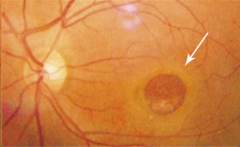

50歲+可能患老年性黃斑變性

黃斑位于眼底,是我們看清外界物體的重要部位。如果黃斑發生病變,那么視力便會受到嚴重損害。

50歲以上的中老年群體更容易患上老年性黃斑變性,這是一種衰老性改變,是常見的致盲性眼病之一,發病率會隨著年齡增加而增高。

中老年人的黃斑區出現衰退,可能會出現視物模糊、視物變形、視物殘缺等癥狀,如果未及時治療,還有可能造成失明。